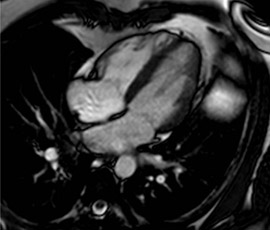

An MRI scan of the heart

“At the end of the six month period patients will be re-assessed and we’ll take various measurements to see if their health has improved. We’ll also be doing MRI scans of the heart of a third of participants to look for physical changes before and after the HAPPY programme, along with using state of the art ultrasound machines to measure changes in the thickness of the walls of the neck arteries.